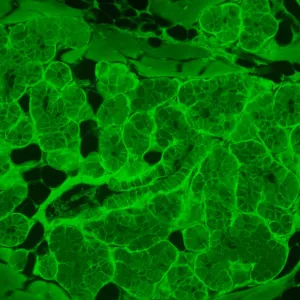

MAGUS Lum V500L – это инвертированный микроскоп для исследований люминесцентным методом в отраженном свете и методами светлого поля и фазового контраста в проходящем свете. Для люминесценции используются фильтры, оптимально подходящие для работы с флюорохромами DAPI, FITC и TRITC. Инвертированная конструкция позволяет изучать образцы в лабораторной посуде – чашках Петри, колбах и проч. Высота посуды может составлять 55 мм, а при отклоненном штативе – 165 мм. Оптика рассчитана на толщину дна посуды 1,2 мм. Микроскоп отлично подходит для исследовательской работы и рутинной лабораторной диагностики, может использоваться для обучения студентов вузов.

В качестве источника возбуждения люминесценции выступает светодиод мощностью 5 Вт и с ресурсом работы 50 000 часов без замены. Фильтров возбуждения три – для флюорохромов DAPI, FITC и TRITC. Светодиодное освещение более экономичное и простое в обслуживании, чем ртутное, поэтому рекомендуется для обучения в вузах. Светодиоды сохраняют постоянство цветовой температуры, быстро включаются и выключаются, не перегреваются при длительной работе.

- Фильтры возбуждения люминесценции для флюорохромов DAPI, FITC и TRITC

| Флуоресцентный модуль | фильтры (флюорохромы): DAPI, FITC, TRITC | |

| Фильтры возбуждения люминесценции: тип фильтра, длина волны возбуждения / дихроичное зеркало / длина волны запирания | DAPI, 365/35 нм / 400 нм / 450/65 нм; FITC, 475/40 нм / 500 нм / 535/45 нм; TRITC, 525/45 нм / 565 нм / 595/60 нм | |